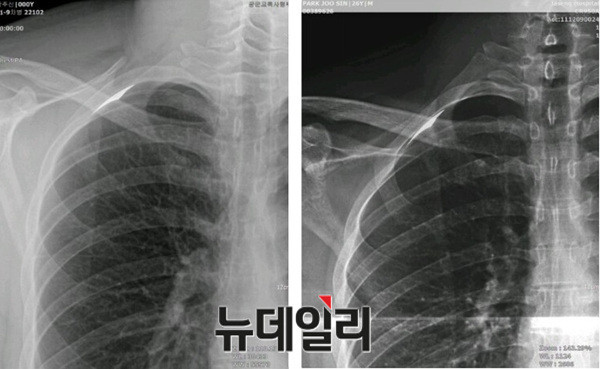

- ▲ 주신씨 명의의 자생병원 엑스레이(왼쪽)와 공군훈련소 입소당시 촬영한 엑스레이 비교사진. '양승오 박사 사건' 피고인들은 자생엑스레이 우측 늑골부위에서 볼 수 있는 석회화 현상이 공군엑스레이에서는 보이지 않는다며, 피사체를 동일인으로 볼 수 없다는 주장을 펴고 있다. ⓒ 뉴데일리DB

이날 증인신문에서는 류OO 교수가 1심 재판부에 제출한 감정서 내용 중, 검찰 감정사항 1번 ‘석회화 현상의 존재 여부’에 대해서 여러 차례 의견을 바꾼 사실도 드러났다.주신씨 명의의 자생엑스레이-공군엑스레이 비교판독결과 나타나는 석회화 현상의 존재 여부는, 주신씨 명의 영상자료 외부 감정과정에서 핵심 쟁점 중 하나였다.

피고인들은 자생병원 X-Ray를 보면, 오른쪽 제1늑골부위에 석회화 현상이 나타나지만, 주신씨가 공군 입대 당시 찍은 X-Ray에는 이런 모습이 전혀 보이지 않는다며, 이는 “두 엑스레이의 피사체가 동일인이 아니라는 사실을 반증한다”고 설명했다.

주신씨 명의의 엑스레이 피사체가 동일인이 아니라는 피고인들의 주장이 사실로 확인된다면, 이는 “박주신씨가 부당한 방법으로 병역을 면탈했다”는 피고인들의 주장에 힘을 실어주는 유력한 증거가 된다.